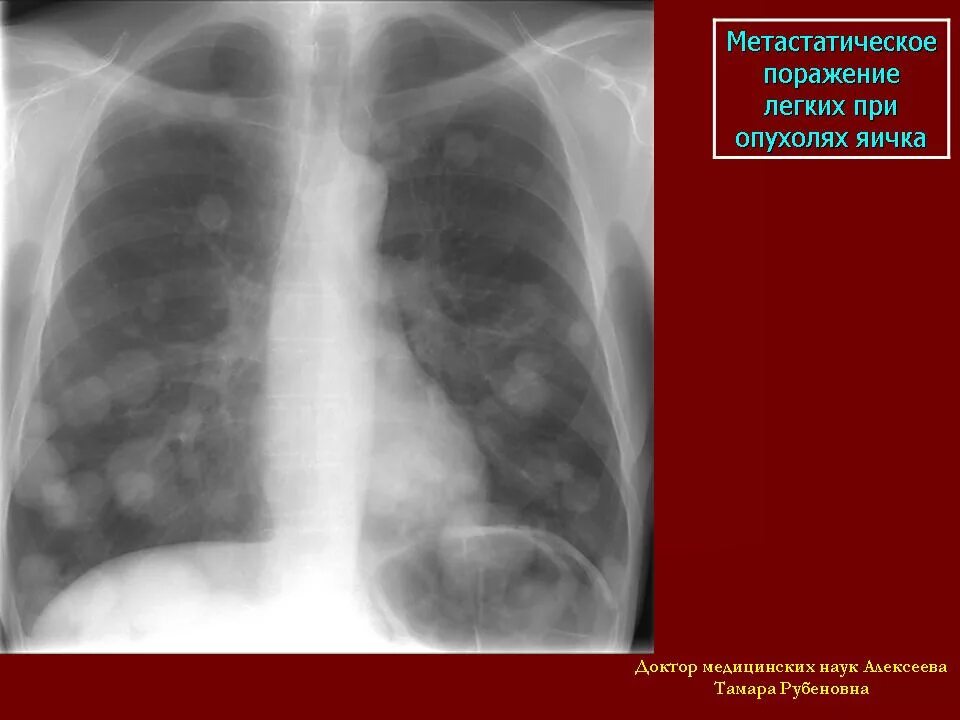

Образование в легком форум